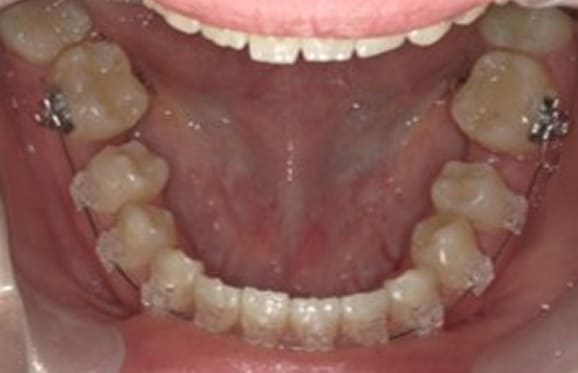

● 歯根が折れ保存不可の歯を抜歯して、そのスペースに八重歯を並べた症例

藤沢デンタルオフィスの虫歯や破折で抜歯後の部分矯正